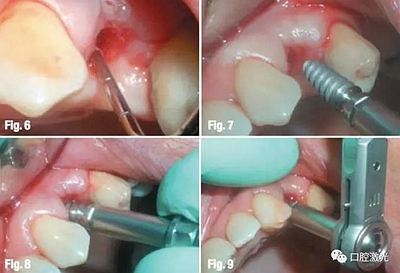

當(dāng)?shù)竭_(dá)適合深度后,再沿水平方向適當(dāng)延伸。先手動(dòng)安裝種植體,在利用扭力扳手設(shè)定為廠家推薦最大扭矩進(jìn)行安裝,直到將種植體安裝牢固。

隨后,設(shè)置激光參數(shù)為功率2W、脈沖能量100mJ、20%水、20%氣,對手術(shù)區(qū)域附近進(jìn)行牙齦整形,以便于取模。隨后設(shè)置激光功率為1W、脈沖能量50mJ、10%水、10%氣,對種植體周圍軟組織進(jìn)行輕度去角質(zhì)化處理。整個(gè)預(yù)備和取模的時(shí)間不超過15分鐘,因此種植體穩(wěn)定度極高。